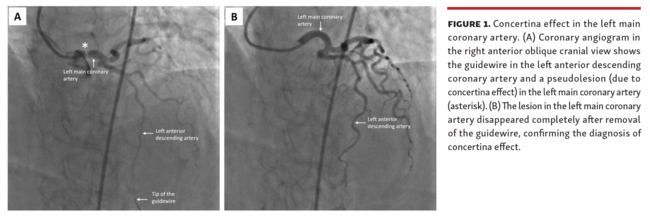

A Balanced Heavy Weight wire (Abbott Vascular) was used for crossing the LAD artery obstruction. We deployed a coronary stent (3.0 x 18 mm, Promus Element stent; Boston Scientific) in the proximal LAD, covering the lesion successfully. However, following stent deployment, we found an additional lesion in the left main coronary artery (Figure 1A and Video Series), which was persistent even after intracoronary nitroglycerin injection.

Catheter-induced dissection of the left main coronary artery was considered. Previous angiography views confirmed that the new lesion had appeared just after wiring the LAD artery. This indicated a possible concertina effect in the left main. The guidewire, following the stent placement, was cautiously removed, keeping the floppy portion in the left main for an easy repeat access if required. On withdrawal of the guidewire, the lesion in the left main disappeared completely (Figure 1B and Video Series).